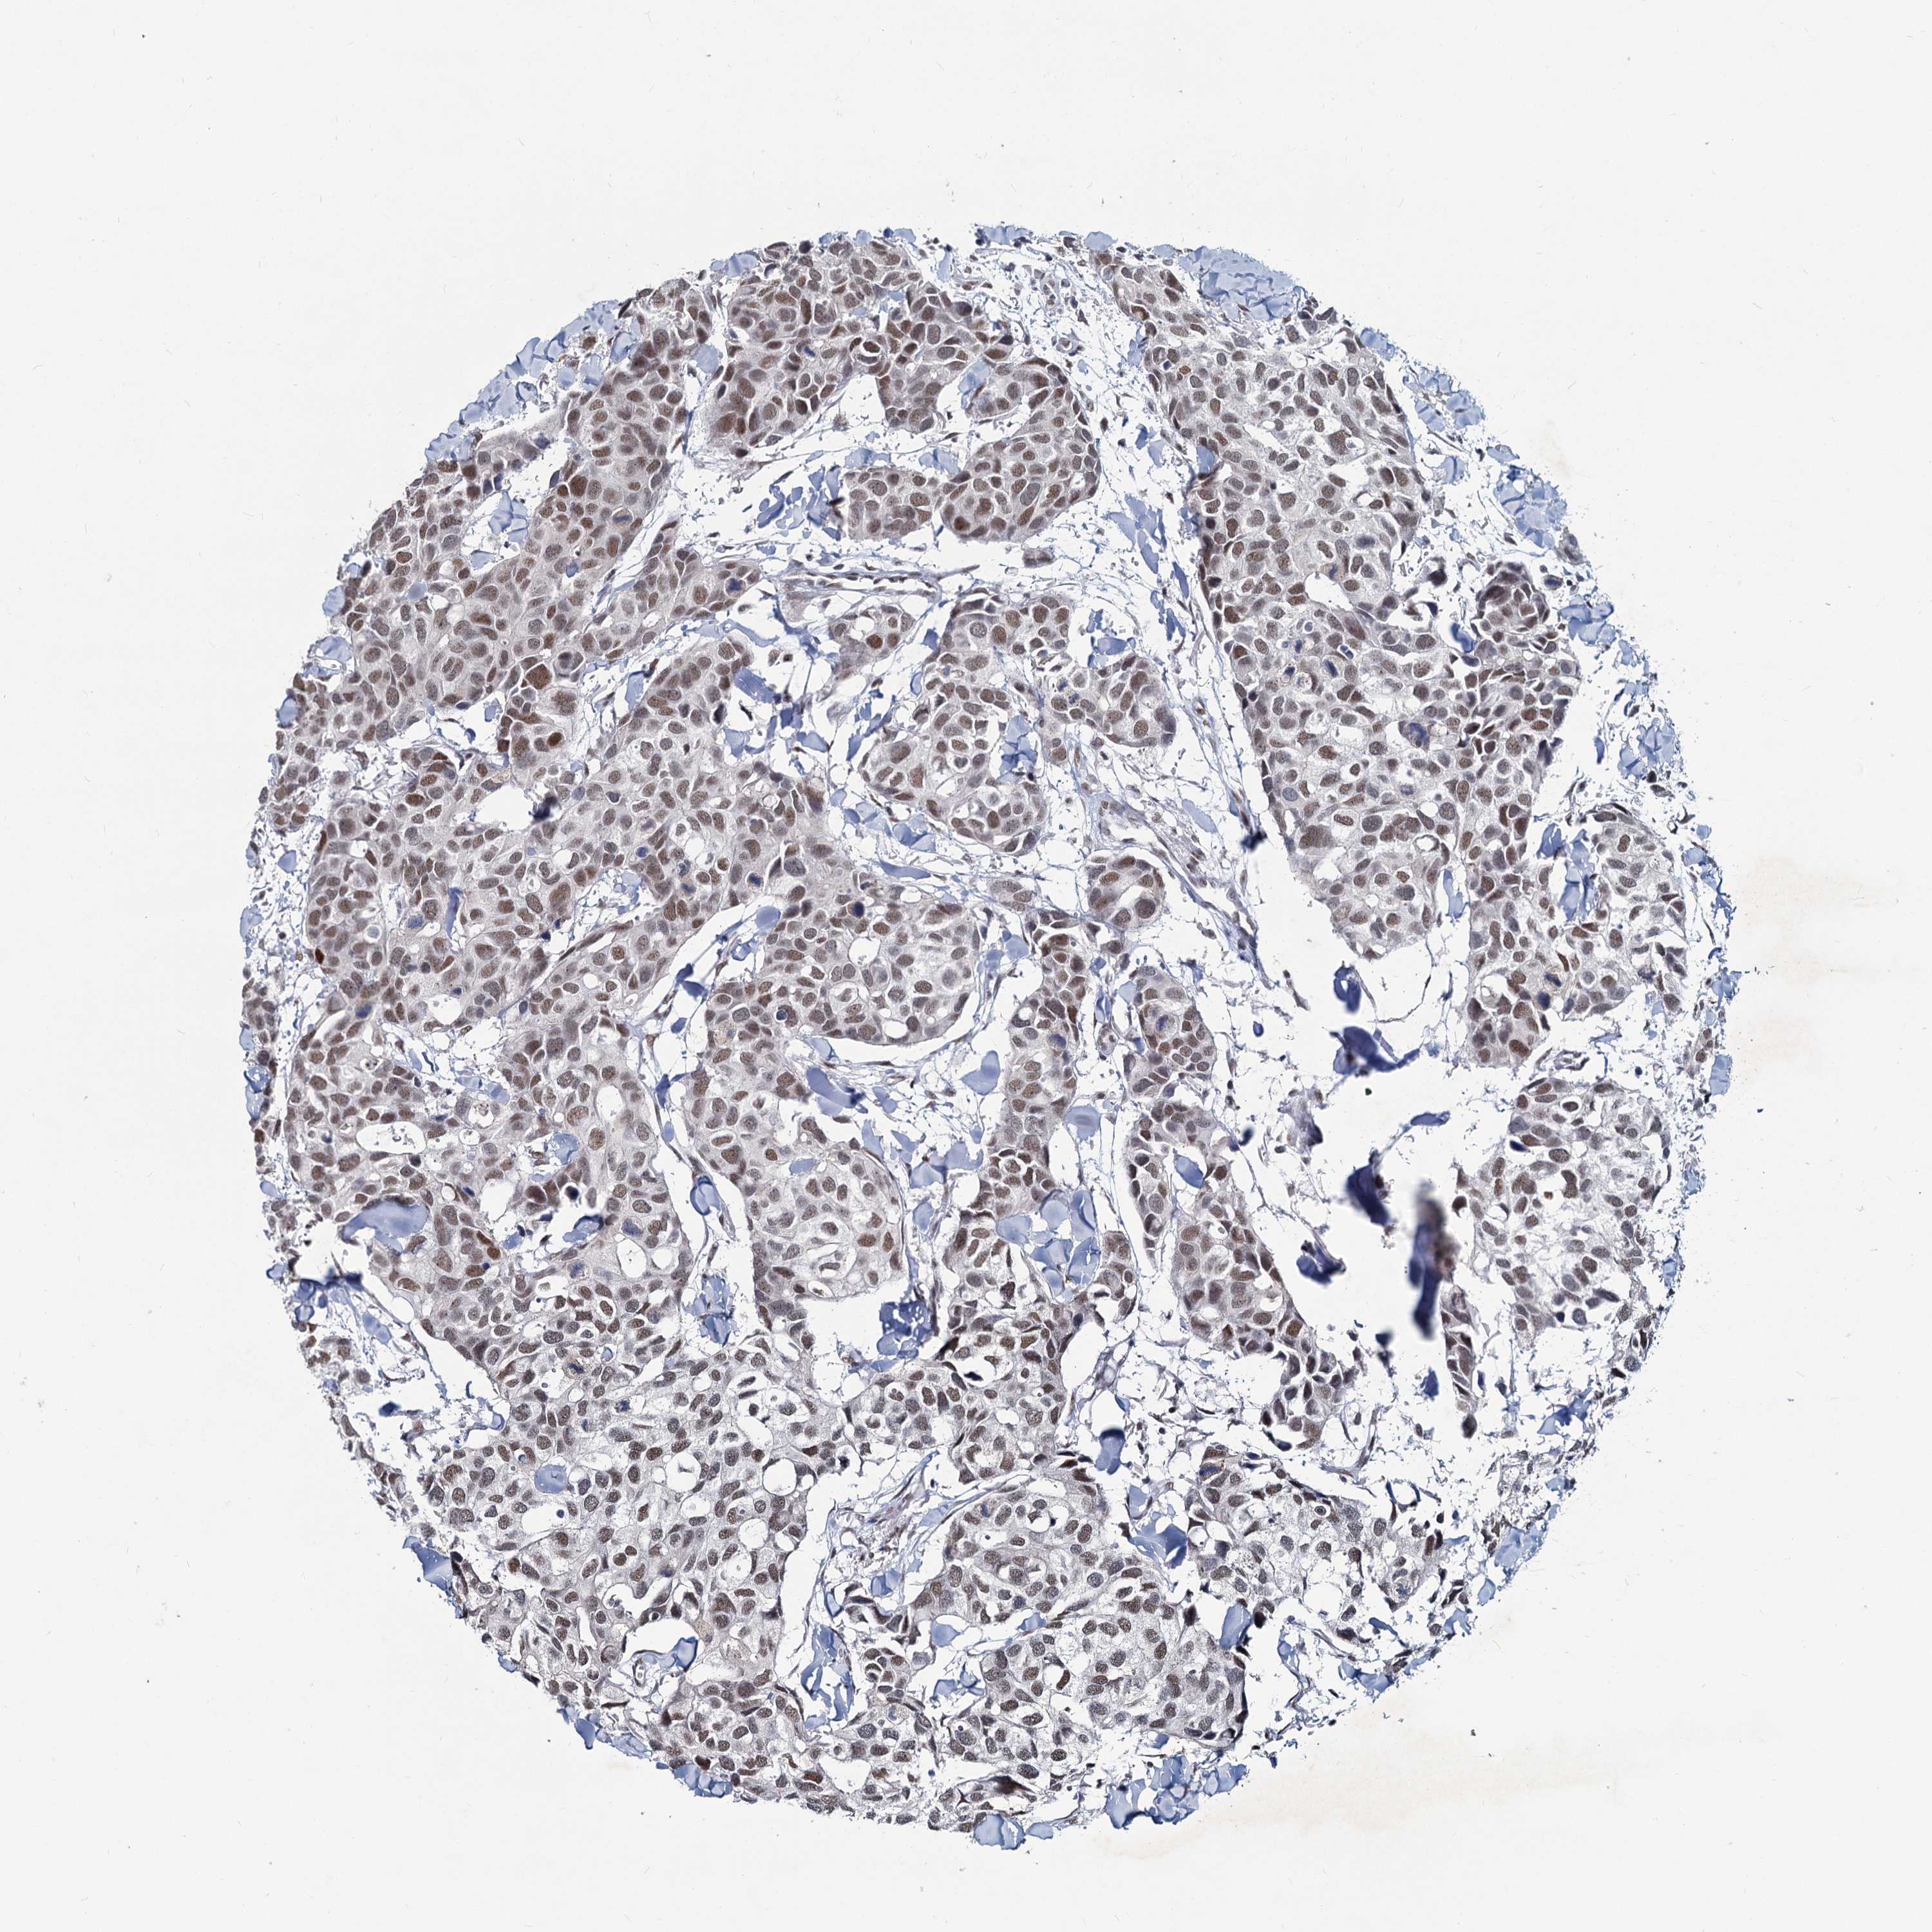

CANCER BREAST CANCER Show tissue menu

BRCA TCGA BRCA VALIDATION PROTEIN EXPRESSION